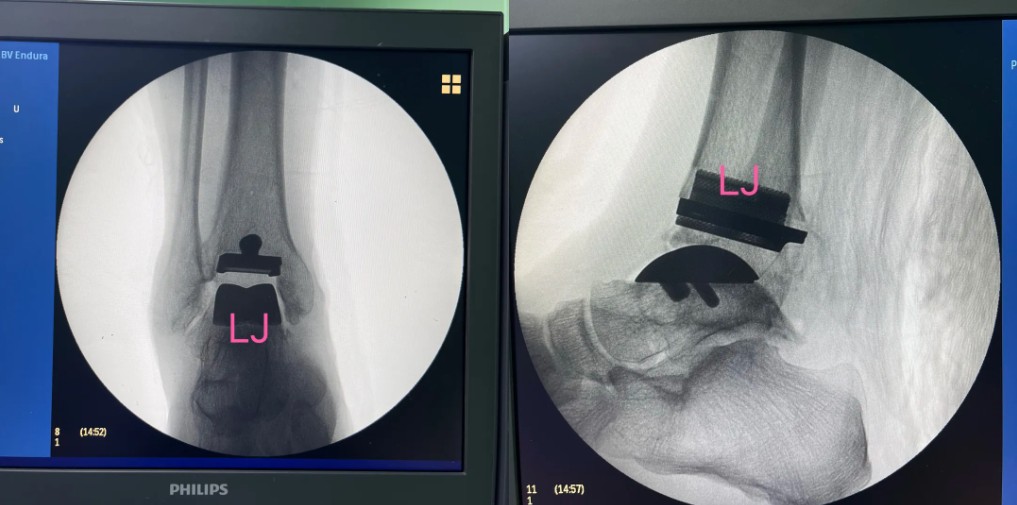

術(shù)后影像

3D打印個(gè)性化定制導(dǎo)板

基于患者踝關(guān)節(jié)三維影像數(shù)據(jù),3D打印專屬截骨導(dǎo)板和植入的假體,確保假體與骨骼匹配。

數(shù)字化導(dǎo)板引導(dǎo)下,截骨誤差小于1毫米,極大提升手術(shù)安全性。